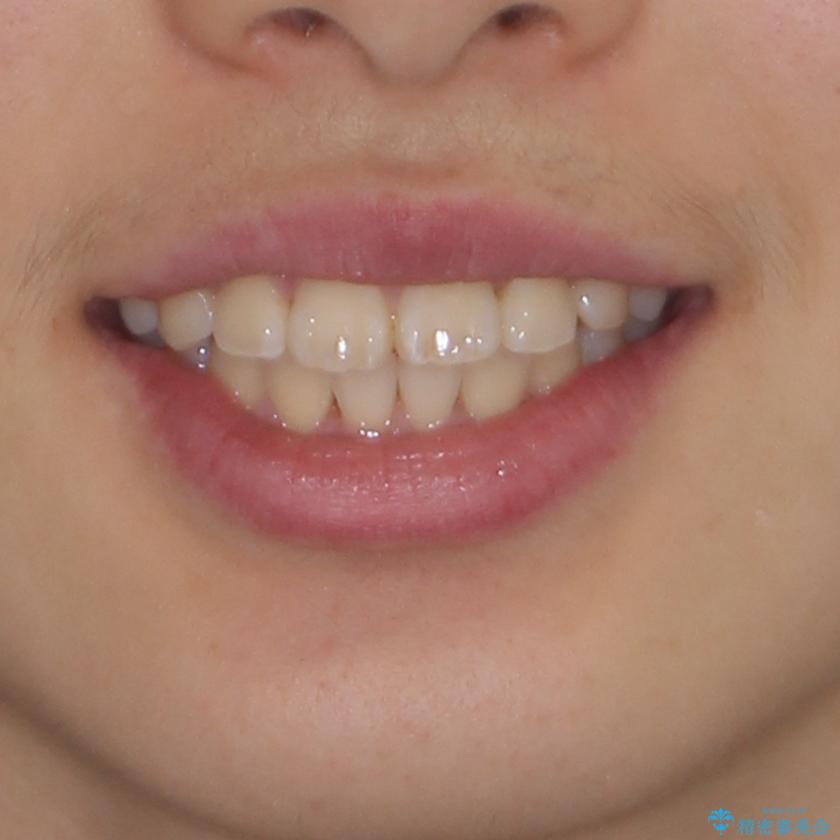

前歯のデコボコを短期間で治療 目立たないワイヤー矯正

中学生と言うこともあり、1年強の短期間で終了しました。

歯磨きがしっかりとできないと虫歯になるリスクがありましたが、治療期間中は清潔な状態を保っていただけました。